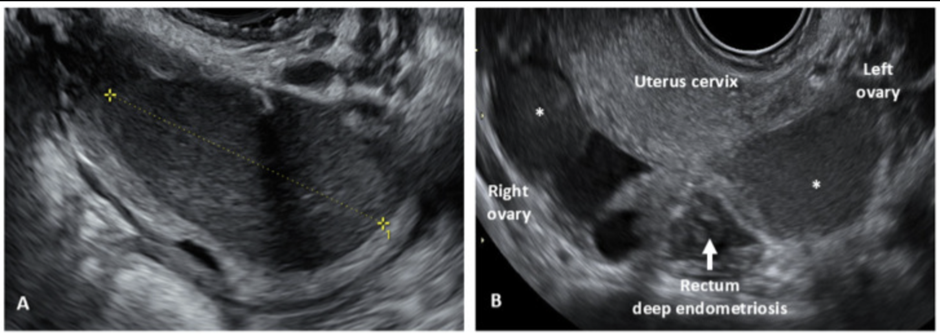

2) Ultrasound / MRI

Ultrasound of pelvis or MRI to diagnose and map the endometriosis are both equally accurate and useful. Specialised imaging can detect:

- endometriomas (chocolate cyst)

- the location of deep infiltrating endometriosis

- adenomyosis or fibroids

- pelvic adhesions and organ fixation

However, imaging requires both experience and the right technique. Not all general gynaecologists are trained in ultrasound to detect endometriosis, and not all radiologists are trained to interpret endometriosis accurately on MRI.